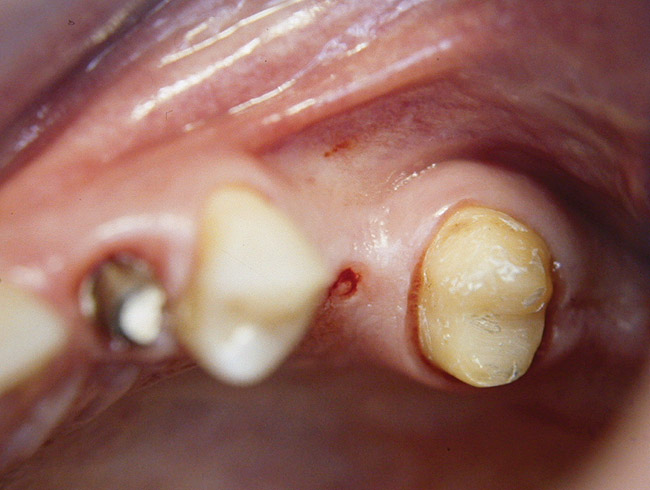

Second-stage surgery was performed after 4 months (Figure 8); healing abutments were placed and the soft tissue was allowed to heal for 5 more weeks. Then, splinted porcelain-fused-metal (PFM) crowns supported by custom gold abutments were delivered (Figure 9 and Figure 10).

Figure 9  Final implant-supported PFM restorations.

Figure 9